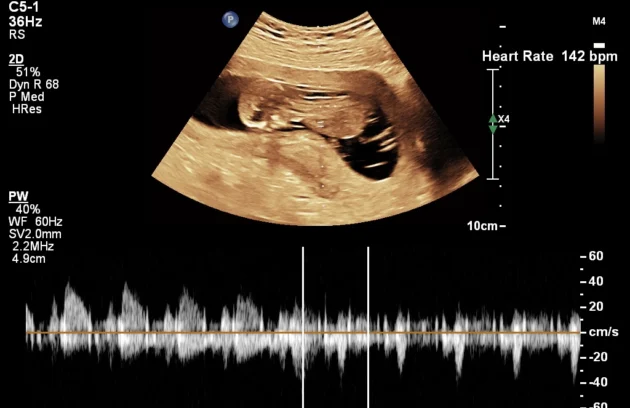

Doppler Scan

Doppler Ultrasound (Fetal Doppler) – Kathmandu A Doppler ultrasound measures fetal blood flow and circulation in the uterus and umbilical cord. This Color Doppler imaging uses sound waves to visualize blood flow in the…